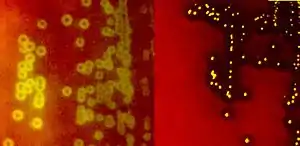

برخی از گونههای استرپتوکوکها میتوانند بیماریهایی مانند فارنژیت استرپتوکوکی (گلودرد چرکی)، مننژیت، پنومونی (سینه پهلو)، اندوکاردیت، بادسرخ و فاسئیت نکروزان (قانقاریا) را ایجاد کنند. با این وجود، بیشتر گونههای استرپتوکوک، غیربیماریزا هستند و به عنوان فلور (همزیست) دهان، پوست، روده و سیستم تنفسی فوقانی محسوب میشوند. همچنین استرپتوکوکها به عنوان یکی از اجزای ضروری تولید پنیر امنتال (پنیر سوئیسی) به حساب میآیند. استرپتوکوکها بر اساس ویژگیهای همولیتیک (همولیز خون) طبقهبندی میشوند. گونههای آلفا همولیتیک موجب اکسیداسیون آهن در گلبولهای قرمز میشوند و آگار خون دار را سبزرنگ مینمایند. گونههای بتاهمولیتیک موجب از هم گسیختگی کامل گلبولهای قرمز میشوند بطوریکه ناحیهای عاری از گلبولهای قرمز در اطراف کلنی باکتری در آگار خون دار دیده خواهد شد. گونههای گاما همولیتیک، هیچ نوع همولیزی تولید نمیکنند.[4] گونههای بتاهمولیتیک استرپتوکوکها، با استفاده از سروتیپ بندی لنسفیلد (به انگلیسی: Lancefield serotyping)تقسیم بندی میشوند. این تقسیمبندی بر اساس حضور وجود کربوهیدارتهای خاصی در دیواره سلولی باکتری است[5]. تاکنون ۲۰ سروتیپ لنسفیلد یعنی از A تا V (غیر از I و J) توصیف شدهاست. از دیدگاه پزشکی، مهمترین استرپتوکوکها عبارتند از گروه آلفا همولیتیک (استرپتوکوک پنومونیه و استرپتوکوکهای ویریدانس)، گروه بتا همولیتیک (استرپتوکوکهای گروه A و استرپتوکوکهای گروه B).